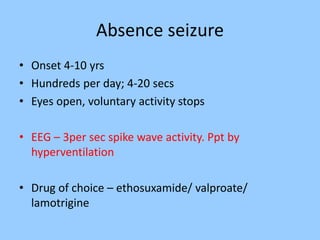

2. Case studies are presented with clinical histories and EEG findings to illustrate different pathologies. Treatment options are also mentioned for many of the conditions.

3. International standards for EEG electrode placement and recording parameters are reviewed. Characteristics of different EEG waves, amplitudes, and patterns are described.